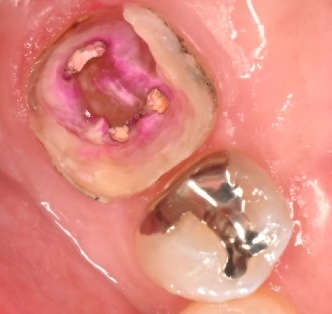

見た目で「黒い部分」を取り除いただけでは不十分な場合があります。もし感染した歯質が残ったまま壁を作ってしまうと、内部でむし歯が再発してしまうからです。

そこで当院では、歯科医師の目視だけでなく、**「う蝕検知液(カリエスディテクター)」**という専用の薬液を使って、むし歯の取り残しがないかを確認します。

この写真は、検知液を塗布した状態です。もし、むし歯(感染した部分)が残っていれば、その部分だけが赤く染まります。 赤く染まる部分が完全になくなるまで、慎重に、徹底的に汚れを除去していきます。